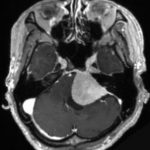

図1 さまざまな部位に発生した髄膜腫のMRI画像所見

頭蓋底髄膜腫